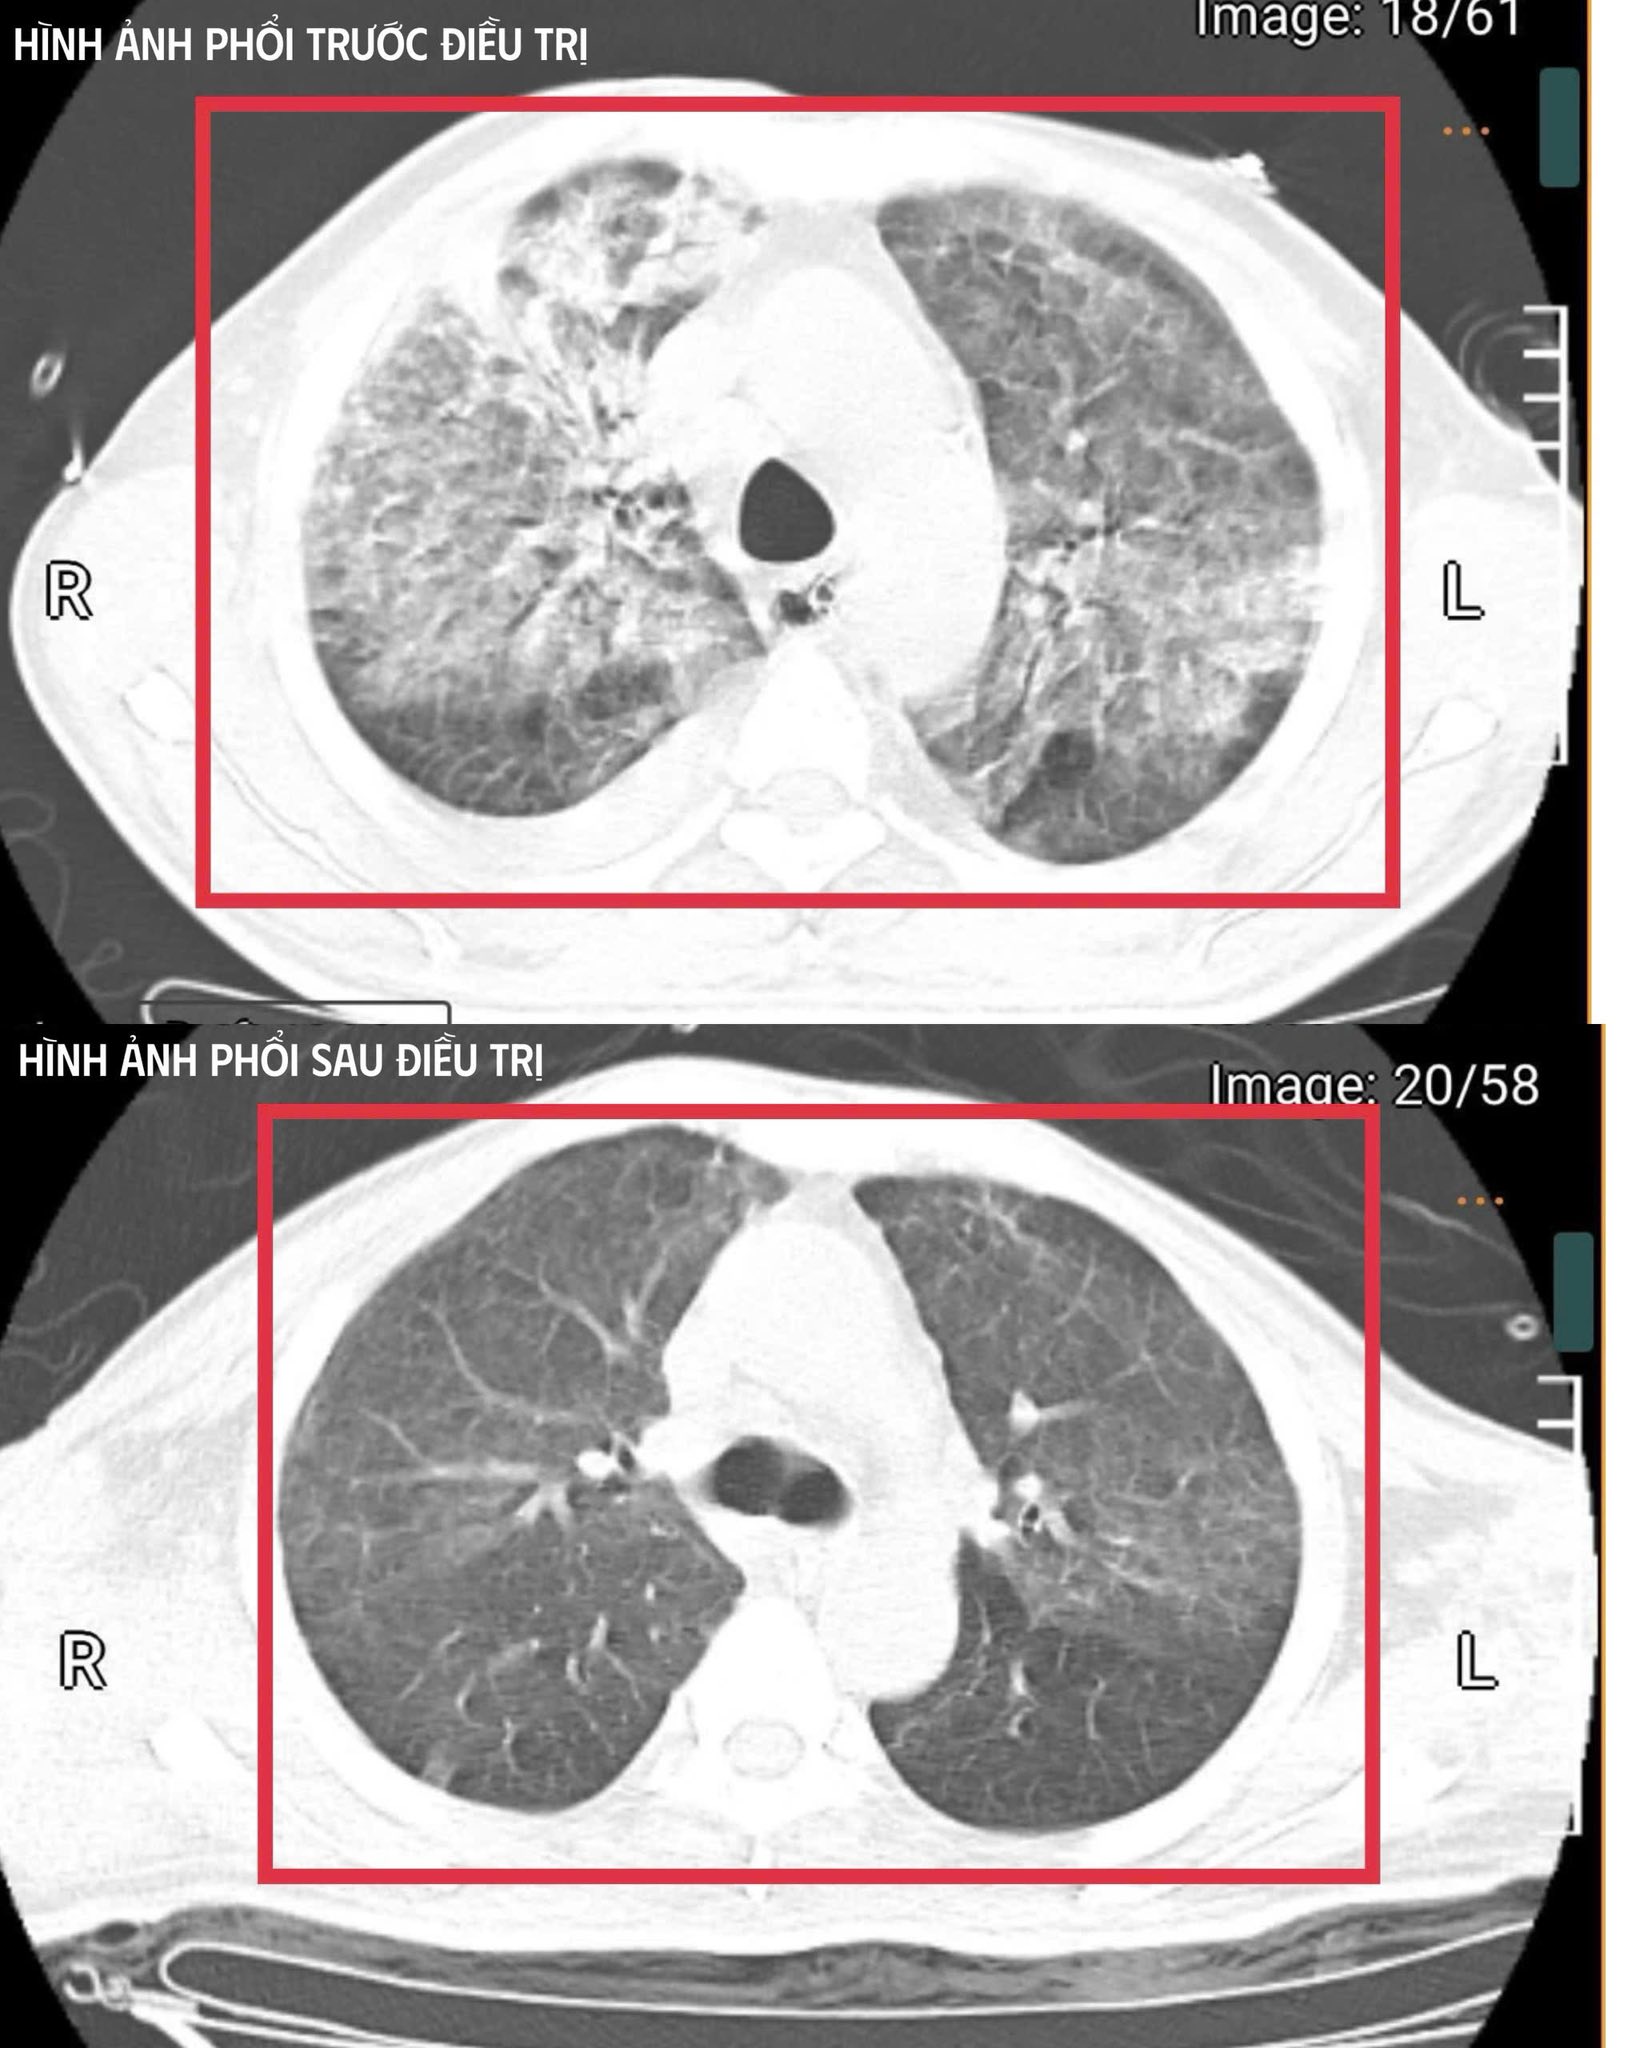

Người bệnh cai được thở máy qua mở khí quản, tập lại hô hấp tự nhiên và phục hồi vận động. Trong ba tuần điều trị tích cực tại Khoa Cấp cứu, các bác sĩ tiếp tục tối ưu kháng sinh, kiểm soát chặt chẽ đường huyết, hỗ trợ dinh dưỡng và phục hồi chức năng sớm. Người bệnh hồi phục từng bước: Tỉnh táo hoàn toàn, tự thở khí phòng với SpO₂ 99%, huyết áp 130/80 mmHg, cơ lực chi trên đạt 5/5, chi dưới 4/5, đủ điều kiện ra viện và tiếp tục theo dõi ngoại trú.